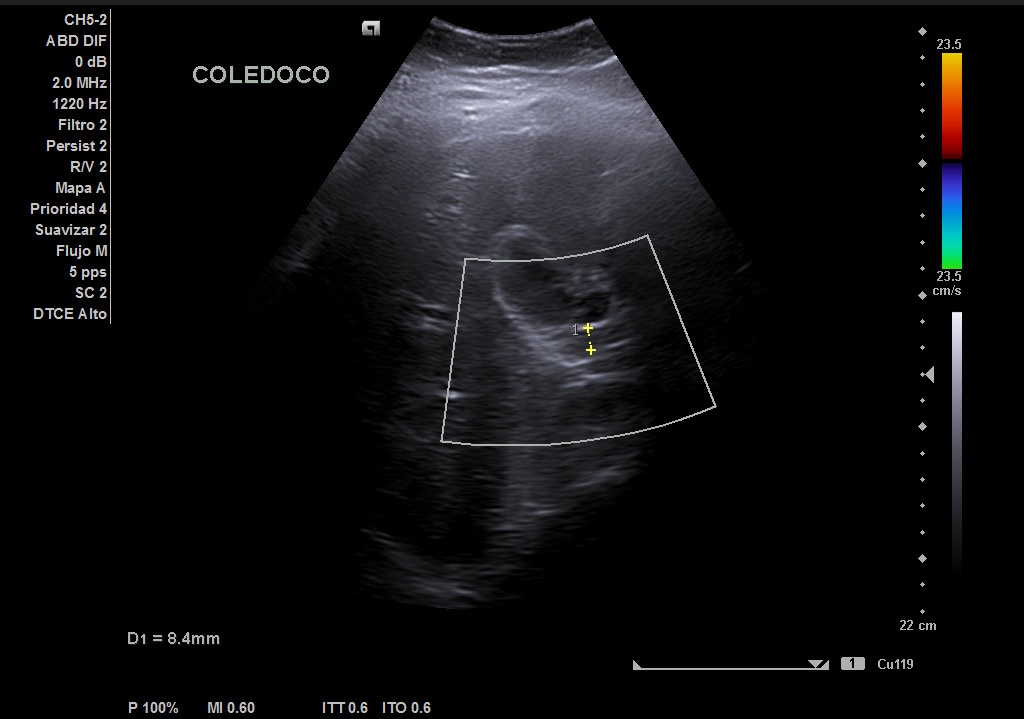

Hallazgos ecográficos

Hígado de tamaño, forma y ecoestructura conservadas, con parénquima homogéneo. Vena porta de calibre conservado. Colédoco dilatado, de 8,8 mm. Vesícula biliar de paredes gruesas y edematizadas (5,4 mm) en cara posterior, con contenido ecogénico y 2 microlitiasis en su infundíbulo.